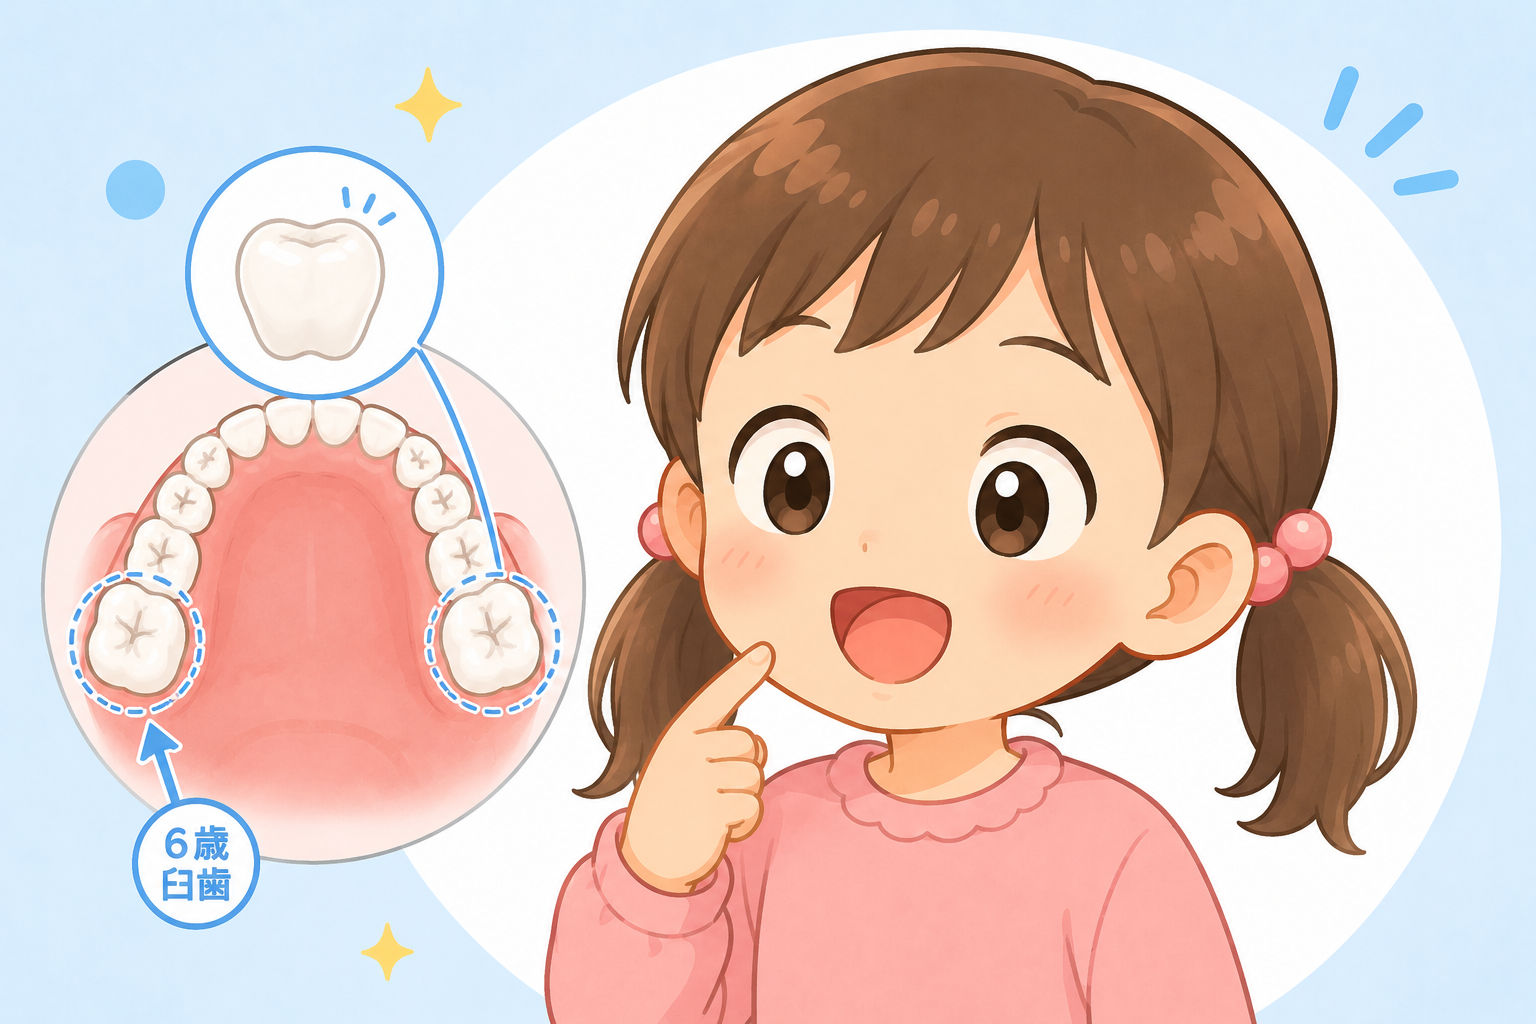

加齢や歯周病の影響で歯茎が下がり、「歯根」と呼ばれる部分が露出することがあります。

歯根にはエナメル質が存在せず、象牙質がむき出しになるため、歯全体が黄色く見えることがあります。